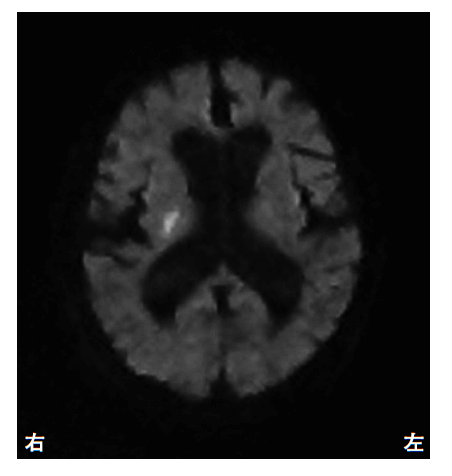

突然の左不全片麻痺を呈して搬送された患者の発症後3時間の頭部 MRI の拡散強調像(別冊No. 1)を別に示す。最も考えられるのはどれか。\n